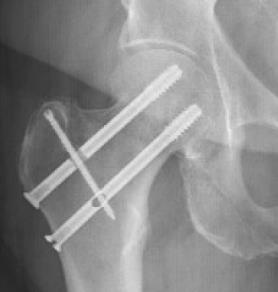

SimpliFix Hip System

• The SimpliFix Hip System is a percutaneous fixation construct for minimally displaced or non-displaced intracapsular femoral neck fractures, designed to mitigate complications seen with parallel screw constructs or dynamic hip screw alone. The system pairs two large-diameter cannulated screws with a targeted headless cross screw that keys through a slot in the superior screw to add rotational control. Using a dedicated targeting arm, the surgeon selects 0 mm (no dynamization) or 3 mm (controlled settling) of compression to help resist femoral neck shortening while maintaining native neck length and femoral offset.

• The cross-screw technique enhances rotational stability and helps prevent lateral head migration, supporting alignment and reducing the risk of additional shortening. Preserving femoral neck length correlates with improved pain and function in postoperative recovery, making controlled compression and rotational control clinically meaningful endpoints.

• SimpliFix trajectories place an inferior calcar screw for axial support and a central–superior screw oriented toward the anterior–superior head, preserving bone stock while providing a dedicated slot for the cross screw.

• These vectors resist varus collapse and shortening.

• Drive and seat the inferior SimpliFix cannulated screw (Ø 8.3 mm, 16 mm thread, blunt, self-tapping head).

• Assemble the SimpliFix T-handle and retaining bolt; secure the superior SimpliFix screw (ensure fins engage the mating slots).

• Insert the headless cross screw (Ø 3.7 mm) with a T8 driver; power to near seat, then hand-seat to cortex.

• Final verification: anteroposterior and lateral fluoroscopy to confirm reduction, implant positions, and cross-screw engagement with the superior screw slot.